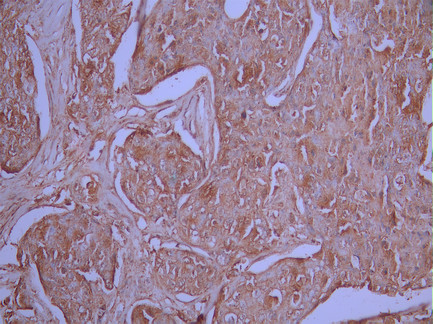

• IHC image of CSB-RA179147A0HU diluted at 1:100 and staining in paraffin-embedded human melanoma cancer performed on a Leica BondTM system. After dewaxing and hydration, antigen retrieval was mediated by high pressure in a citrate buffer (pH 6.0). Section was blocked with 10% normal goat serum 30min at RT. Then primary antibody (1% BSA) was incubated at 4°C overnight. The primary is detected by a Goat anti-rabbit polymer IgG labeled by HRP and visualized using 0.05% DAB.